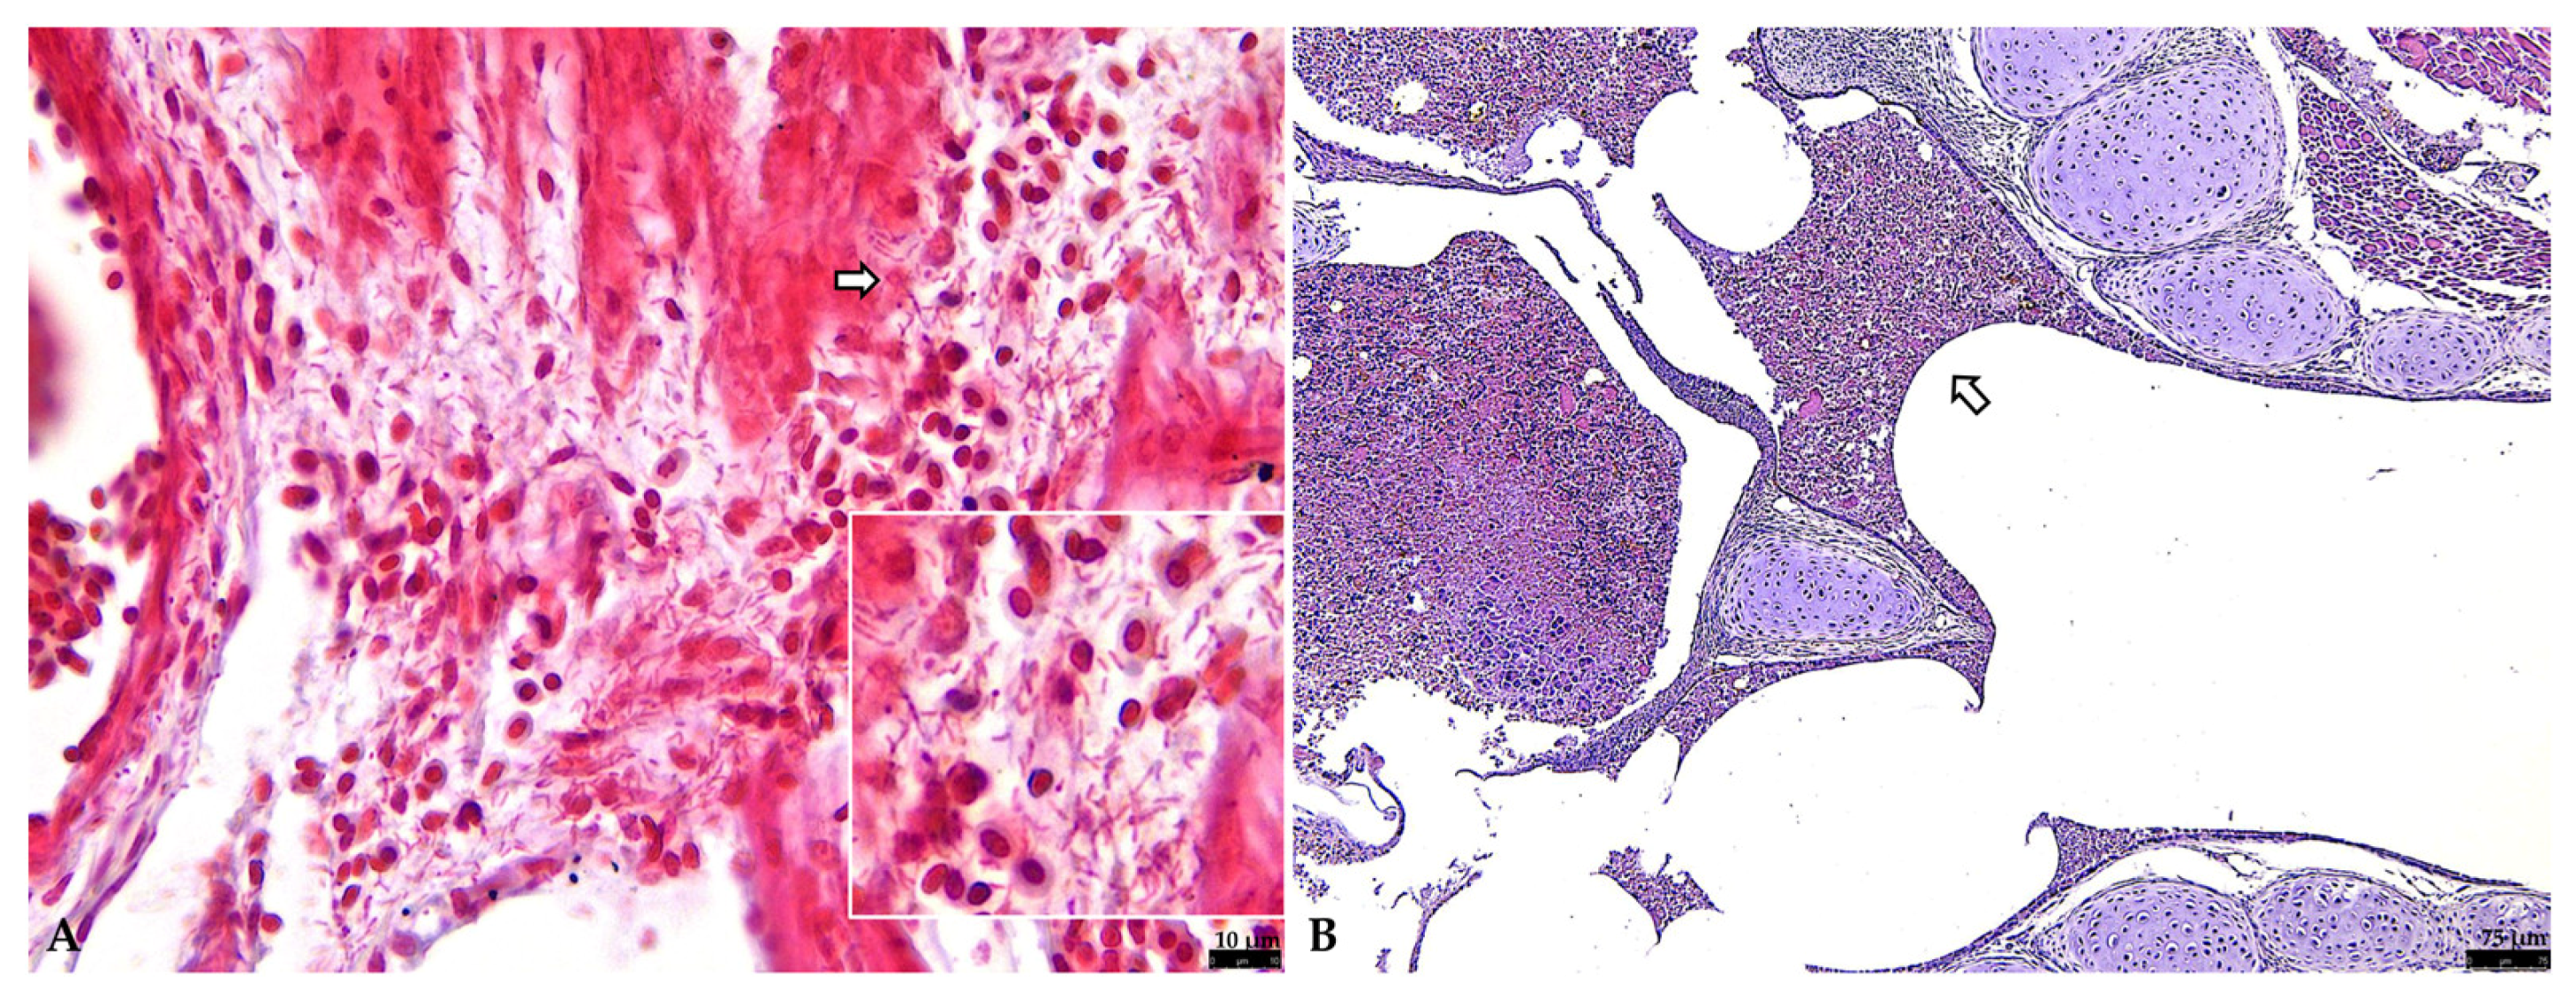

3.2.1. Respiratory Tract

3.2.2. Liver

3.2.3. Other Organs